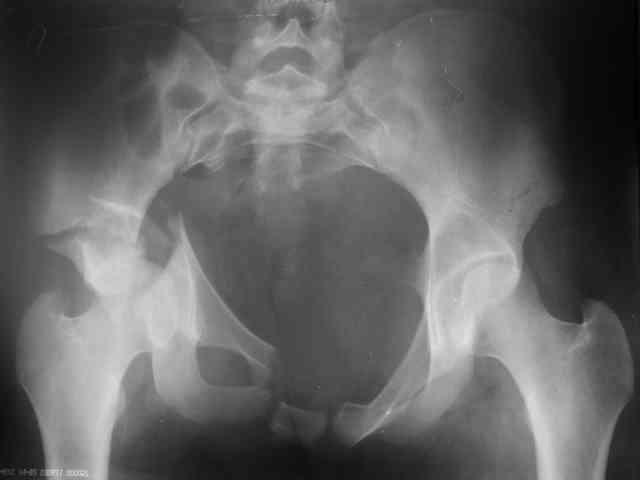

Трудности возникли сразу после рассечения большой ягодичной мыцы - короткие наружные ротаторы едва ли определялись - головка и шейка (как видно на

снимке) ушли в таз, пришлось воспользоваться дистрактором( ручные попытки выдернуть голову из под проксимального фрагмента - безуспешны) Шарнирный дистрактор - великое изобретение, без него репозиция была просто невозможна.

P.S. в приложении R пациентки с похожей проблемой доступа.. за исключением того, что перелом

двухколонный. Вертлугу лечили Y доступом.